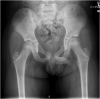

Recurrent traumatic hip dislocation in an 8-year-old boy

Pediatric traumatic hip dislocations (PTHD) are rare and represent around 5% of all pediatric dislocations. Associated bony or soft tissue injury can occur as often as 17%-25% of the time. We report a case of an 8-year-old boy presenting a posterior hip dislocation after a low-energy trauma, which was initially managed with closed reduction and bed rest for 1 week. Two days after hospital discharge, he suffered a recurrent posterior hip dislocation. He was now managed with 4 weeks of bed rest and lower limb skin traction followed by 1 week of no weight-bearing on crutches. With 6 months of follow-up, he is asymptomatic, walking autonomously, with complete and painless range of motion of the affected hip and no major radiographic changes. Pediatric traumatic hip dislocation is a rare and challenging injury that should be managed promptly. Currently, there is no protocol concerning treatment in the literature and its largely dependent of patient and parents' cooperation.